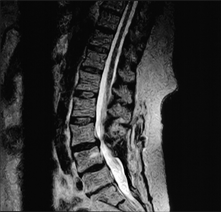

Above, are lumbar spine images of a patient who had undergone back surgery but continued to experience pain. The MRI image on the left was acquired with the patient lying down. It shows a normal alignment of the vertebrae. However, when the patient was scanned in an upright position on the same MRI scanner on the same day (image on the right), a dramatic spinal instability was clearly revealed. This problem, visible only when the patient was scanned upright, would have gone undiagnosed on a conventional, lie-down MRI scanner.